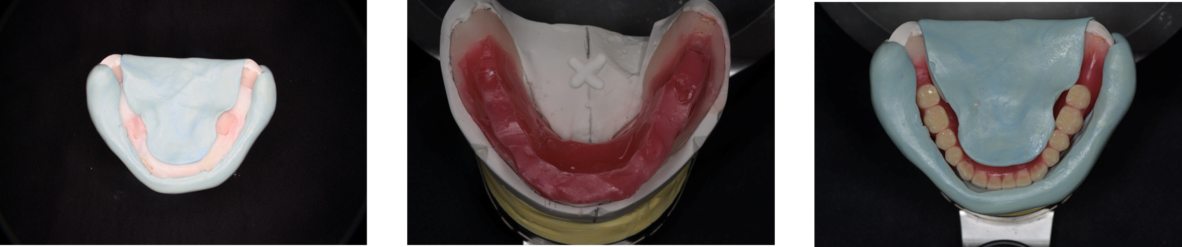

最新な入れ歯(義歯)デジタルデンチャー

現在最も新しい入れ歯(義歯)の作製方法として注目されているのが、このデジタルデンチャーになります。

デジタルデンチャーは、特徴の1つとして現在の入れ歯をコピーすることが可能となります。まだまだ改良の余地はありますが、現在の入れ歯(義歯)をスキャンして、短期間で入れ歯(義歯)を完成する事が可能となります。

入れ歯のデザイン

コンピューター上で入れ歯(義歯)をデザインする事ができます。非常に簡単にデザインができることも、デジタルデンチャーの特徴の1つになります。

デジタルデンチャーセット

完成したデジタルデンチャーです!

非常に粘膜面のコピーが上手くいっており、入れ歯の形が非常に再現されています。

デジタルデンチャー(お口の中)

お口の中でも問題なくセットができました。外形の変化が少ないので違和感が少ないと考えました。